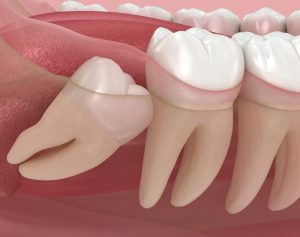

x-ray of impacted wisdom teethWisdom teeth extractions are surgical procedures that remove one or more third molars, commonly known as wisdom teeth, when they cause problems or pose risks to oral health. These teeth typically emerge between ages 17 and 25, but often lack adequate space in the mouth, leading to impaction, crowding, or other complications that require professional removal.

• Impacted Wisdom Tooth Removal: Addresses teeth that cannot emerge properly due to insufficient space or abnormal positioning. Impacted teeth may be completely buried in bone, partially emerged, or angled against adjacent teeth.

• impacted wisdom toothImpacted Wisdom Teeth: Patients whose wisdom teeth cannot emerge properly due to insufficient space, abnormal positioning, or obstruction by other teeth benefit from extraction to prevent complications.